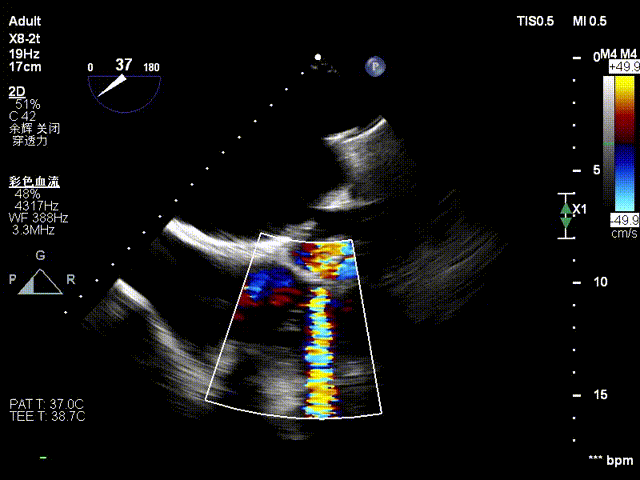

经右颈内静脉穿刺建立通路,置入18Fr鞘管,将K-Clip®输送系统送达右心房。依托三维经食管超声心动图(3D TEE)联合 DSA 双模态引导,经验精准定位瓣环,于后隔交界(P-S commissure)植入14T规格K-Clip®,前后交界(A-P commissure)植入16T规格K-Clip®,实现瓣环多点精准环缩。每枚夹子释放后,团队实时通过超声评估瓣叶对合及反流改善情况,严格遵循 “精准定位 - 锚定验证 - 安全解离” 的规范化操作流程,确认无瓣叶损伤、瓣口狭窄及心包并发症后,完成器械解离与撤出。

2. 超声引导下置入大鞘和输送系统

3. 控弯旋转输送器指向靶点,3D MPR平面攻入锁定螺丝